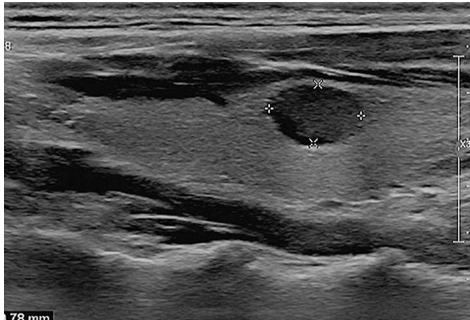

典型病例:如图3所示,1.0cm的TR4类结节在标准体系仅建议随访,而改良策略正确推荐活检,最终确诊为乳头状癌。